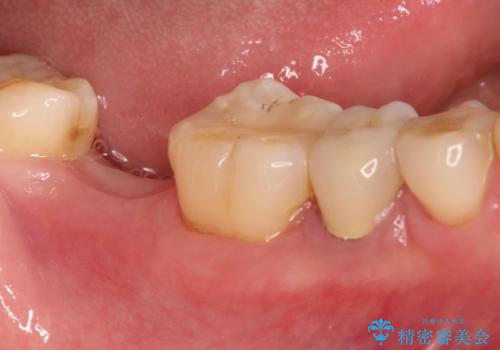

右下の奥歯を抜歯 インプラント治療による咬合回復

- 右下の奥歯をかぶせ物がとれたまま放置しているところに歯を入れたいとのことで来院されました。

精査すると保存が難しいため抜歯をして、インプラントを埋入、かぶせ物を装着する計画としました。

インプラント治療により、周りの歯を削ることなく咬合を回復することができました。